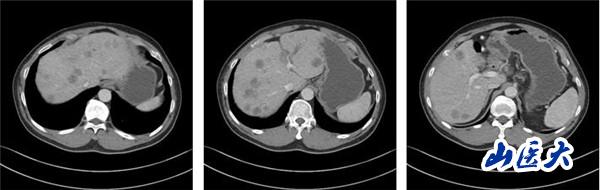

(2022-08-26复查肝脏CT静脉期)

该患者在团队成员仔细阅片、认真讨论下,因患者为PD-L1 CPS高表达人群,TMB-H基因状态。尽管目前国内外胰腺癌诊疗指南并没有对该类型患者指明个体化治疗策略,但通过查阅近年来已经报道的小样本临床研究以及个案报道资料,最终为患者制定了免疫联合化疗治疗策略:PD-1单抗+AG治疗6周期后,PD-1单抗+卡培他滨维持治疗。2022年8月26日,患者再次完善胸腹部CT评价疗效后,达到了大PR(部分缓解)的效果。多达20余处肝转移病灶几乎消失不见,患者可以正常工作生活。